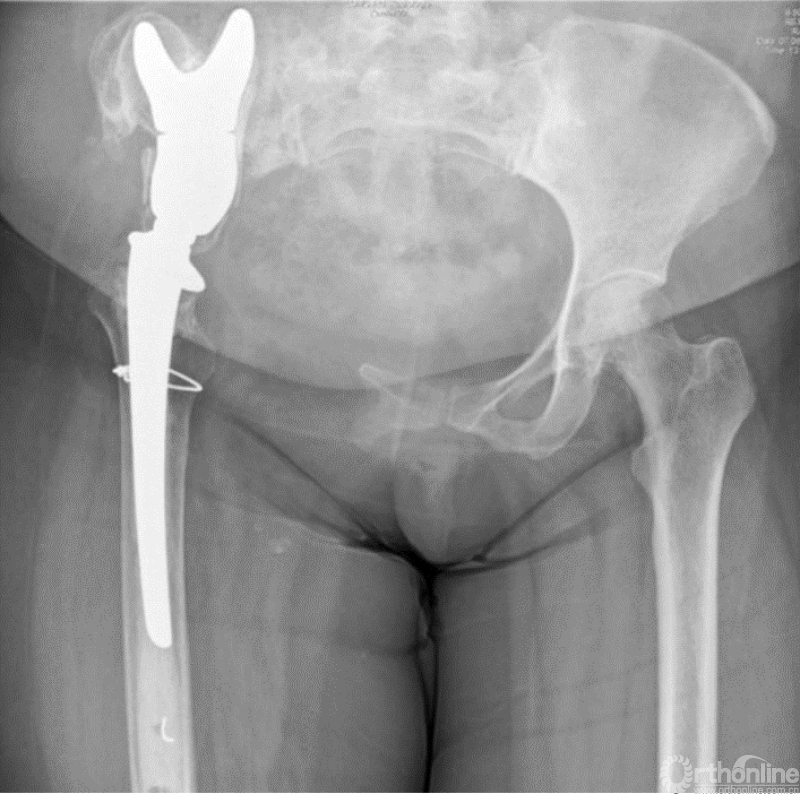

马鞍式假体未与宿主骨形成稳定的骨性连接,整体功能较差,并且并发症发生率较高[2-5](图1)。冰激凌假体与宿主骨的连接更加紧密,但不适合骨盆I区大部分切除的骨缺损,不能重建完整骨盆环[6-10](图2)。组配式半骨盆假体组装灵活,且可进行骨盆环完整重建,但其安装技术要求高,假体组件间存在断裂风险,不匹配得假体与宿主骨锚定将直接影响骨整合,最终易导致松动[1,11-15](图3)。

图1 马鞍式假体